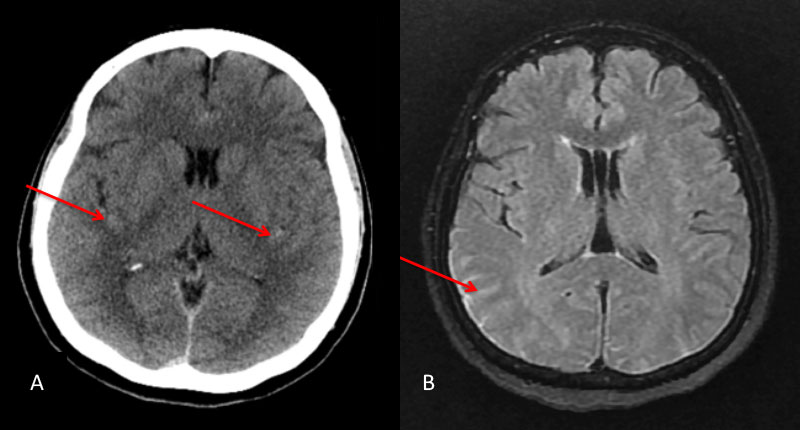

The subararachnoid hemorrhage was focused primarily within the spinal axis of the cervical thoracic and lumbar spine with secondary extension into the brain. A suspicious focal hematoma or mass was observed within the left T4-T5 region with local mass effect representing an intradural extra medullary abnormality with secondary compression of the cord and central myelopathic T2 signal abnormality (Figure 2. A,B,C,D).

Figure 2: A) T1 B) C+ T1 C) STIR D) FS C+ T1 demonstrate focal hemorrhage, contrast enhancement, mass effect, and myelopathic cord signal at T4 (arrows)